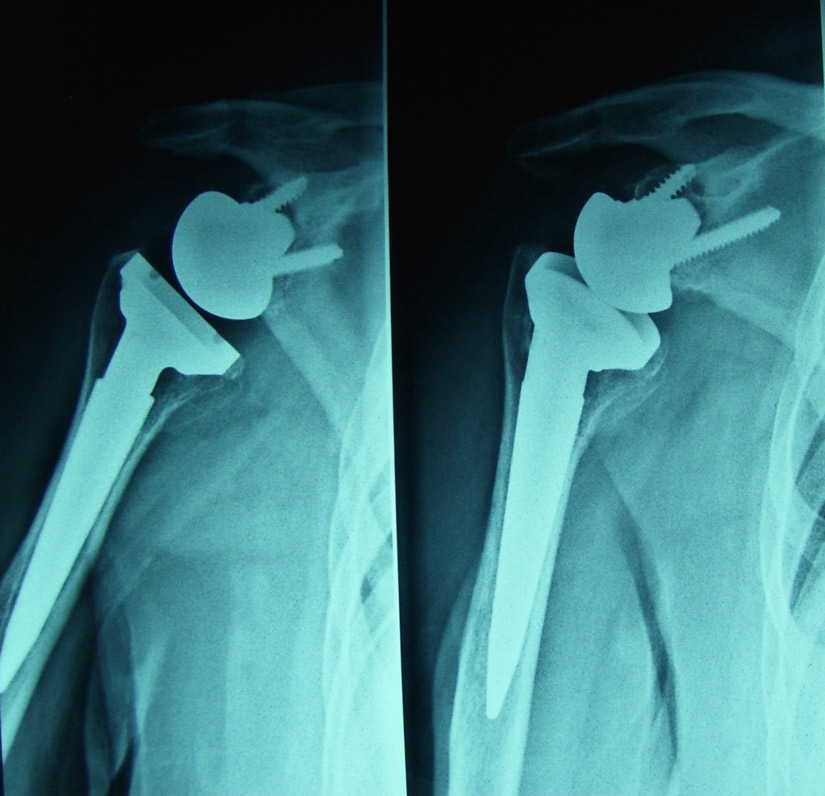

Grazie a questo tipo di intervento si riesce a togliere il dolore e ridare la mobilità a spalle gravemente artrosiche anche con rotture di cuffia irreparabili. Nel caso clinico presentato la paziente lamentava una impossibilità completa alla mobilizzazione attiva della spalla destra.

Fig. 2 Radiografia postoperatoria dopo impianto di protesi inversa